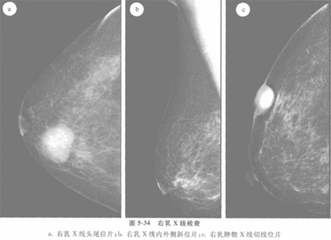

此外,在乳房的钼靶X 线片上,乳腺纤维腺瘤常表现为圆形或卵圆形密度均匀的阴影及其特有的环形透明晕,亦可作为鉴别诊断的一个重要依据。乳腺增生病患者若临床表现不典型或没有明显的经前乳房胀痛,仅表现为乳房肿块者,特别是单侧单个、质硬的肿块,应与乳腺纤维腺瘤及乳腺癌相鉴别。

②钼靶X光照片,对于诊断乳腺纤维瘤是很有帮助的,但只有少数有条件的大医院才有,检查费也比较高,其中还包含有阅片医生水平高低的因素;